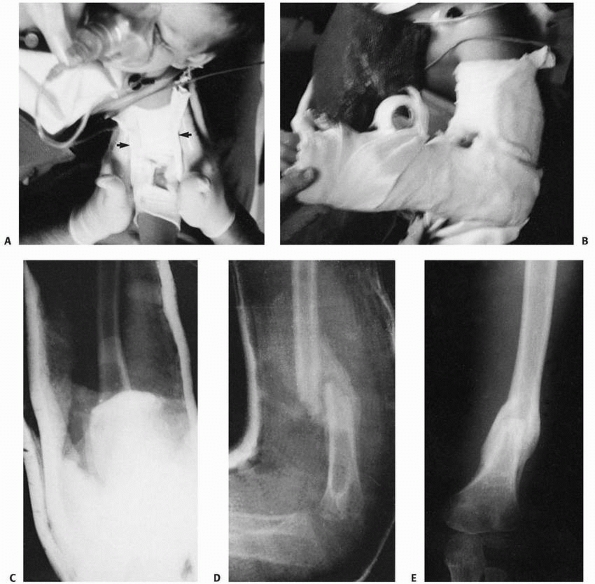

primarily on the anatomic location of fracture. Ada and Miller4

divided scapular fractures into categories of acromion, spine,

coracoid, neck, glenoid, and body. In their series of children and

adults, fractures occurred most often in the body (35%), followed by

the neck (27%); fractures of the coracoid were least common (7%).4 Thompson et al.540

classified scapular fractures into three broad anatomic locations:

fractures of the glenoid and the glenoid neck, fractures of the

acromion and the coracoid, and fractures of the body (Fig 17-9). Other anatomic location-based scapular classifications have been reported by Imatani261 and by Wilbur and Evans.583

anatomic location of the fracture, with additional subclassifications

based on multiple reported studies (see Fig. 17-9 and Table 17-3).